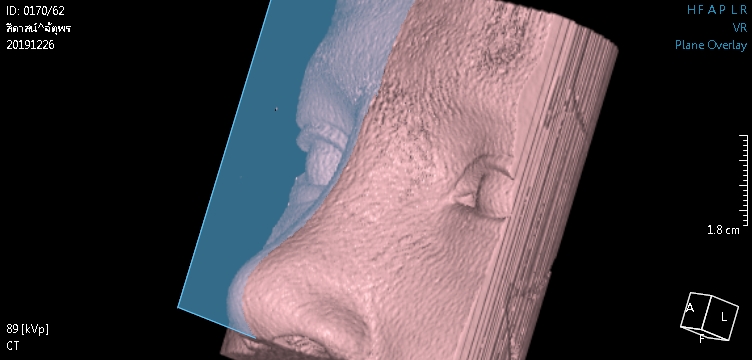

1 ตรวจการเบี้ยวเอียง ปัญหาใหญ่ของการเสริมจมูก ไม่ว่าจะเป็นแบบ openหรือ closed rhinoplasty ก็คือ การเอียง,เบี้ยว คำตอบของผู้ให้กับผู้รับบริการ ที่ไม่ตรงกัน เรามีคำตอบและพิสูจน์ได้ด้วยตาคุณเอง 100% ไม่ว่าจะเป็นที่ไหน โคนหรือปลายจมูก? มากหรือน้อย?

ในกรณีเอียงไม่มาก อาจเป็นสาเหตุให้แกนจมูกใหญ่ หรือ รูจมูกไม่เท่ากันได้ เราสามารถตรวจได้อย่างมั่นใจจากการเห็นภายใน โดยไม่ขึ้นกับอาการบวม เหมือนการตรวจด้วยการมองหรือการคลำ